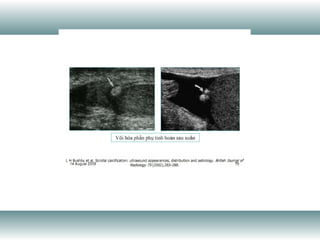

The document is an imaging department report discussing cardiac function measurements. It contains an abbreviation for the ratio of stroke volume (the amount of blood pumped out of the heart with each beat) to end diastolic volume, which is a measurement of cardiac output.